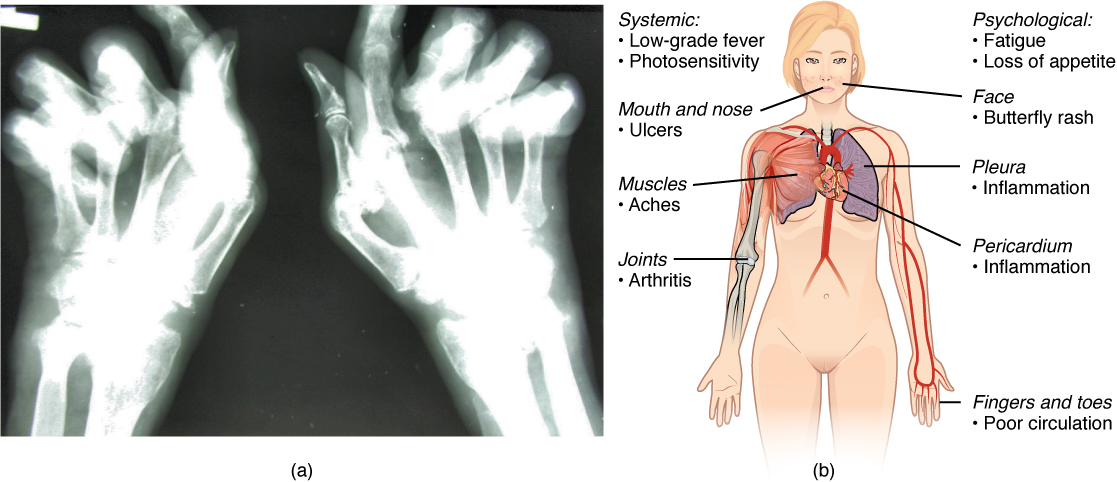

pleuritic pain– is caused during pleurisy, a condition of inflamed pleura caused by a variety of virus or bacterial or other illnesses that travels to the pleurae. The pleuritic chest pain can be defined as a sharp pains that gets worse during inspiration or expiration. Apart from the bacterial or viral infections, pleurisy can also be caused by autoimmune diseases (lupus), pleural disease (i.e., mesothelioma), chest trauma, sickle cell disease, IBD, pulmonary embolism and certain medications etc. (can make an image using bio-render)

friction rub – also known as pleural friction rub, is an involuntary breath sound resulting from the movement of inflamed and swollen pleural surfaces against each other. It can usually better heard during lung auscultation.

Arthritic changes – Arthritis is related to a condition of painful joints due to inflammation or swelling. A type of arthritis is rheumatoid arthritis, it is an autoimmune disease where the immune system attacks the joints, starting with the lining of joints. Rheumatoid arthritis is heavily related to lung problems, about 80% of arthritic patients have lung-related issues, making it the second leading cause of death with rheumatoid arthritis patients. Rheumatoid arthritis caused lung problems are most commonly extra-articular i.e., outside of the joints and involves pulmonary nodules; damage to the lung airways, pleural effusion and interstitial lung disease. In rheumatoid arthritis associated interstitial lung disease the auto-immune system gets over active and attacks the lungs and causes scarring. With time, the scarring build-up leads to difficulty breathing and reduced lung function.